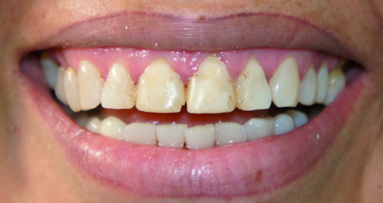

The patient presented in this case was bothered by the look of his overlapping maxillary central incisors (Figs. 20 & 21). His mandibular teeth were also crowded, but for some reason, his concern was only with his maxillary teeth. He had started to hide his smile in front of his friends, feeling embarrassed to show his maxillary teeth. After the full orthodontic examination and discussion about all of the treatment options, including comprehensive orthodontic treatment, the patient chose the removable Inman Aligner system owing to its flexibility in that the wearer is able to remove the appliance for several hours a day and because of its short treatment time. The maxillary left central incisor would have been aggressively prepared had it been treated restora tively.[7–9] By using a simple anterior alignment tech nique, the treatment took only eight weeks to straighten the teeth and a great deal of sound enamel tissue was preserved by conservatively resolving the unattractive appearance of the maxillary teeth (Figs. 22 & 23).